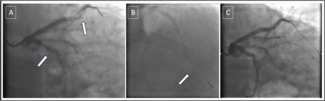

A 52-year-old man with a history of percutaneous coronary intervention (PCI) in the left anterior descending coronary artery was admitted for a facilitated PCI following an anterior ST-elevation myocardial infarction treated with thrombolysis...